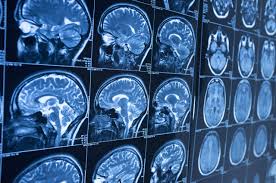

La investigación, titulada “Marcadores neurológicos y neuropsicológicos de feminicidas: una investigación con Resonancia Magnética Funcional”, contó con la colaboración del Centro Conductual para Hombres, la Dirección Nacional de Prisiones y la Fundación EgeDonBosco, y fue desarrollada por los especialistas Dr. Jorge Morillo, PhD; Dr. Peater Stoeter; Lic. Ruthbelkis Suazo; Lic. Jairo Oviedo; Lic. Tatiana González; Dr. Emilio Mota y la Dra. Rea Rodríguez-Raecke.

A los participantes se les realizaron resonancias magnéticas estructurales y funcionales, así como evaluaciones neuropsicológicas y psicológicas, con el fin de analizar diferencias en la estructura cerebral, la respuesta a estímulos emocionales y el funcionamiento cognitivo y conductual.

Entre los hallazgos más relevantes, el grupo de feminicidas mostró menor densidad de materia gris en regiones cerebrales vinculadas al control del comportamiento y la regulación emocional, así como alteraciones en la conectividad de la amígdala, estructura clave en el procesamiento del miedo y las emociones.